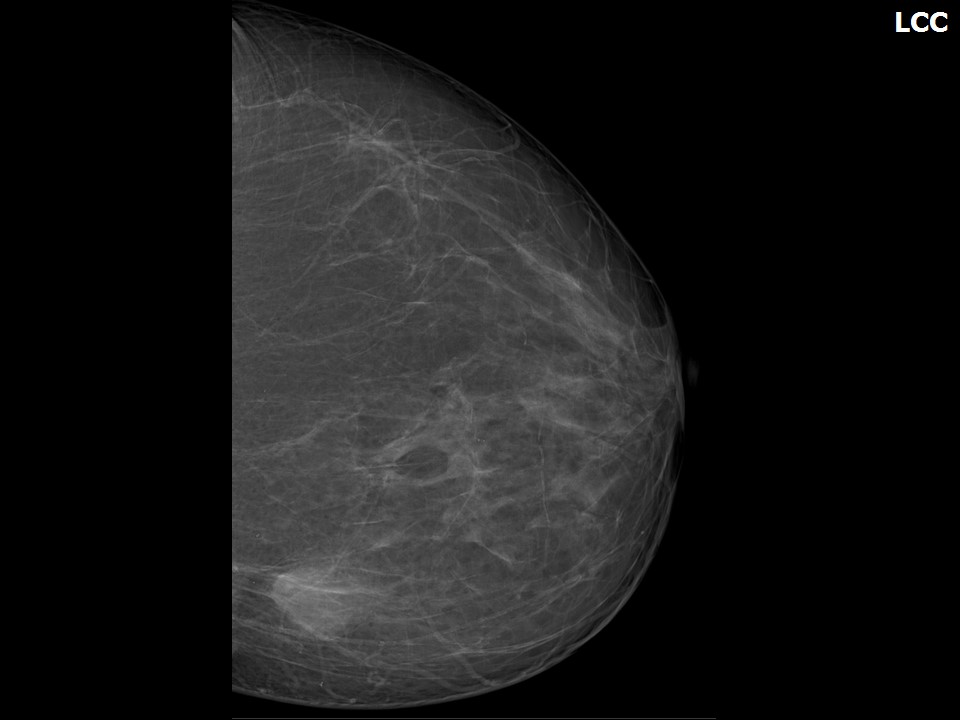

Mammograms

Mammograms are a primary tool for breast examination, particularly for adult women. For teenagers, however, other imaging methods are typically preferred due to the density of developing breast tissue.

Categories of Breast Asymmetry in Imaging

When evaluating breast asymmetry through imaging, healthcare professionals categorize findings into four main types:

- Asymmetry: A one-dimensional difference seen in a single projection

- Global asymmetry: Overall difference in volume or density between breasts

- Focal asymmetry: A density visible in two mammographic views

- Developing asymmetry: Significant changes observed between past and current exams

How do doctors interpret these categories? Each category helps guide further diagnostic steps. For instance, developing asymmetry often warrants additional testing to rule out potential malignancies.

It’s common for two breasts to be different sizes, but they’re usually similar in density and structure. Doctors use mammograms, a type of breast exam, to evaluate the internal structure of the breast.

If your mammogram shows you have asymmetrically dense breasts, the difference in density could be classified into one of four categories if a mass is found:

- Asymmetry. Your breasts are only evaluated using one projection. These images aren’t reliable because they are one-dimensional. Overlapping dense structures in the breast could be difficult to see. If your doctor finds a lesion or abnormality, they’ll call for another three-dimensional imaging test.

- Global asymmetry. This finding shows there’s more volume or density in one breast than the other. Global asymmetry findings are normally the result of hormonal changes and normal variation. If a mass is found, your doctor will request additional imaging.

- Focal asymmetry. These images show a density on two mammographic views, but your doctor can’t fully tell if it’s a true mass. They’ll request further imaging and evaluation to rule out cancerous or abnormal masses.

- Developing asymmetry. This asymmetry type indicates a significant change between past and current exams. The density may be new, or could have increased. These findings are enough to raise suspicion of potentially malignant cells.

If your mammogram indicates asymmetry, your doctor will need additional images to determine if the change in shape or density is normal.